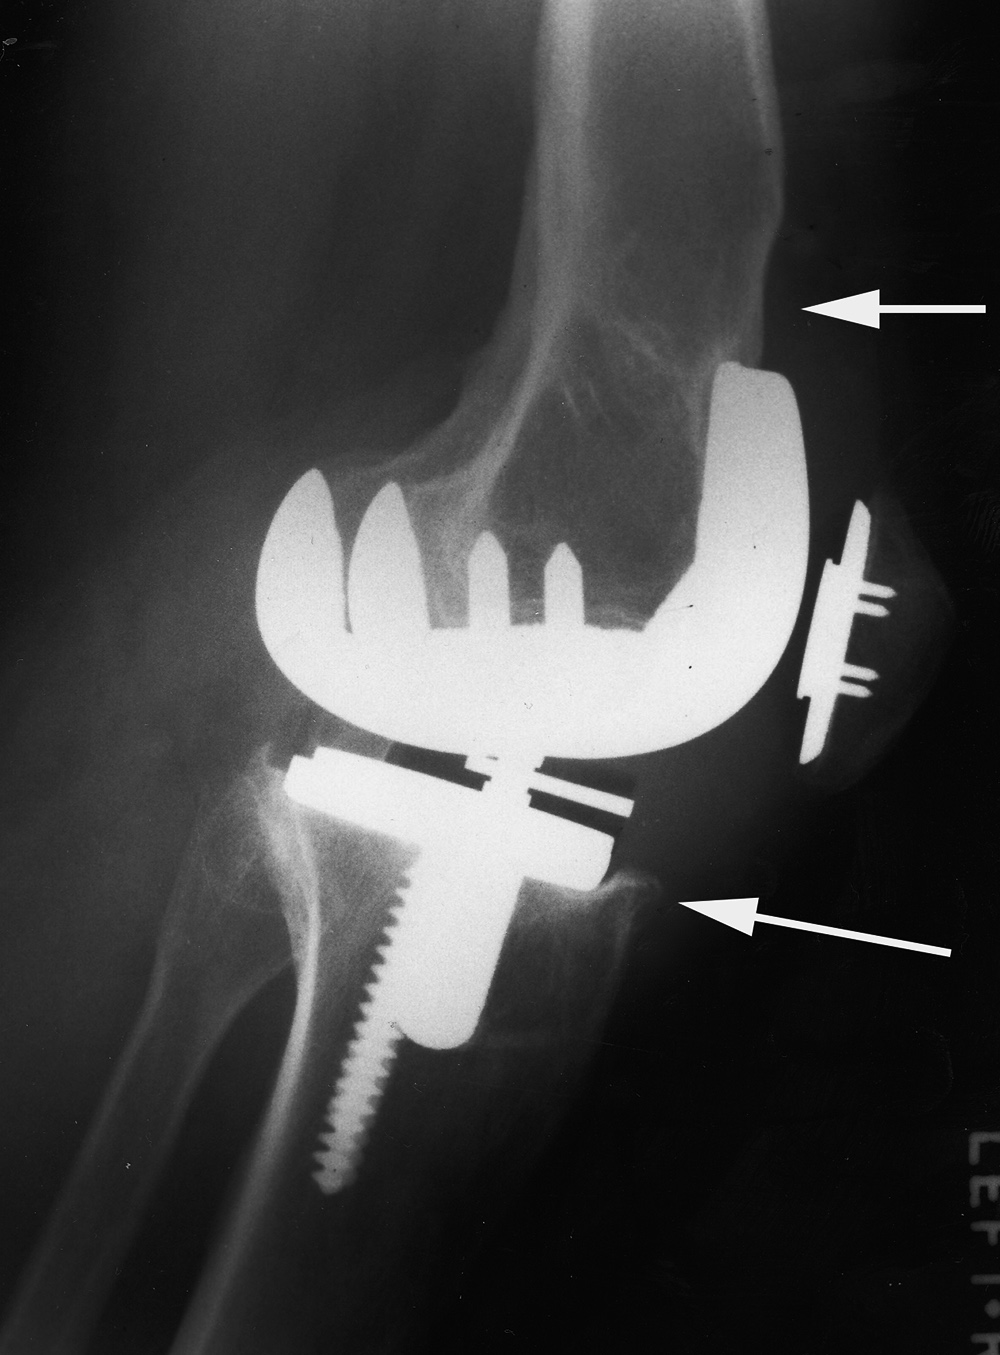

| Rotating-hinge knee implant |

Rotating hinge knee implant failure |

| 69 year-old man with revision of an infected right knee prosthesis (two left panels). A rotating hinge knee implant was placed. Note the antibiotic beads about the medial aspect of the implant. The two fixation screws and wire are from prior surgery. There was implant failure with disruption of the implant six weeks later (two right panels). |